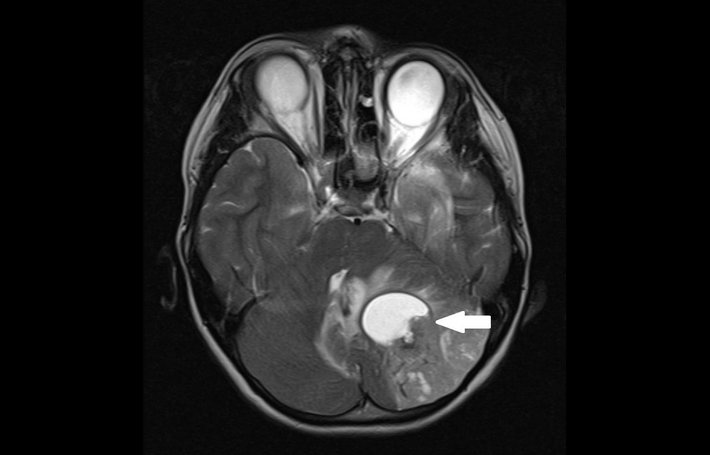

Fallbeispiel: die 34-jährige Angelika W. hat erstmals einen epileptischen Anfall erlitten. Der Ehemann beschreibt, was er an seiner Frau am morgendlichen Kaffeetisch sitzend beobachtet: Es habe zunächst der rechte Arm angefangen zu zucken und dieser sei wenige Minuten später schlaff heruntergehangen. Seine Frau sei aber stets ansprechbar gewesen. In den Monaten vor diesem Vorfall sei ihm eine Wesensänderung und erhöhte Ermüdbarkeit aufgefallen. Manchmal verhalte seine Ehefrau sich ihren Kindern gegenüber merkwürdig, gebe teilweise unpassende Antworten. Sie habe ständig über Kopfschmerzen geklagt. In einer ersten Untersuchung seien dem Hausarzt eine leichte Kraftlosigkeit im rechten Arm und Bein sowie ein leicht hängender rechter Mundwinkel aufgefallen.

Die Kombination aus spezifischen neurologischen Ausfällen - nicht zuletzt dem epileptischen Anfall - und seit längerem bestehenden, wenig fassbaren Beschwerden haben bei Angelika W. zur Diagnose eines Glioblastoms geführt. Das Glioblastom gehört zu den häufigsten, bösartigen Tumoren des Hirngewebes.